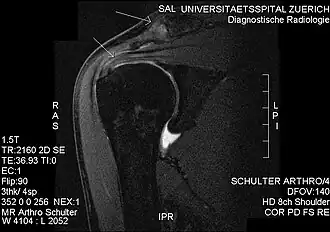

MRI showing subacromial impingement with partial rupture of the supraspinatus tendon, but no retraction or fatty degeneration of the supraspinatus muscle.

Impingement syndrome can be diagnosed by a targeted medical history and physical examination,[13][14] but it has also been argued that at least medical imaging[15] (generally X-ray initially) and/or response to local anesthetic injection[16] is necessary for workup. However, imaging studies are unable to show cause of shoulder pain in diagnosing. For example, MRI imaging would show rotator cuff pathology and bursitis but is unable to specify the cause.[17]